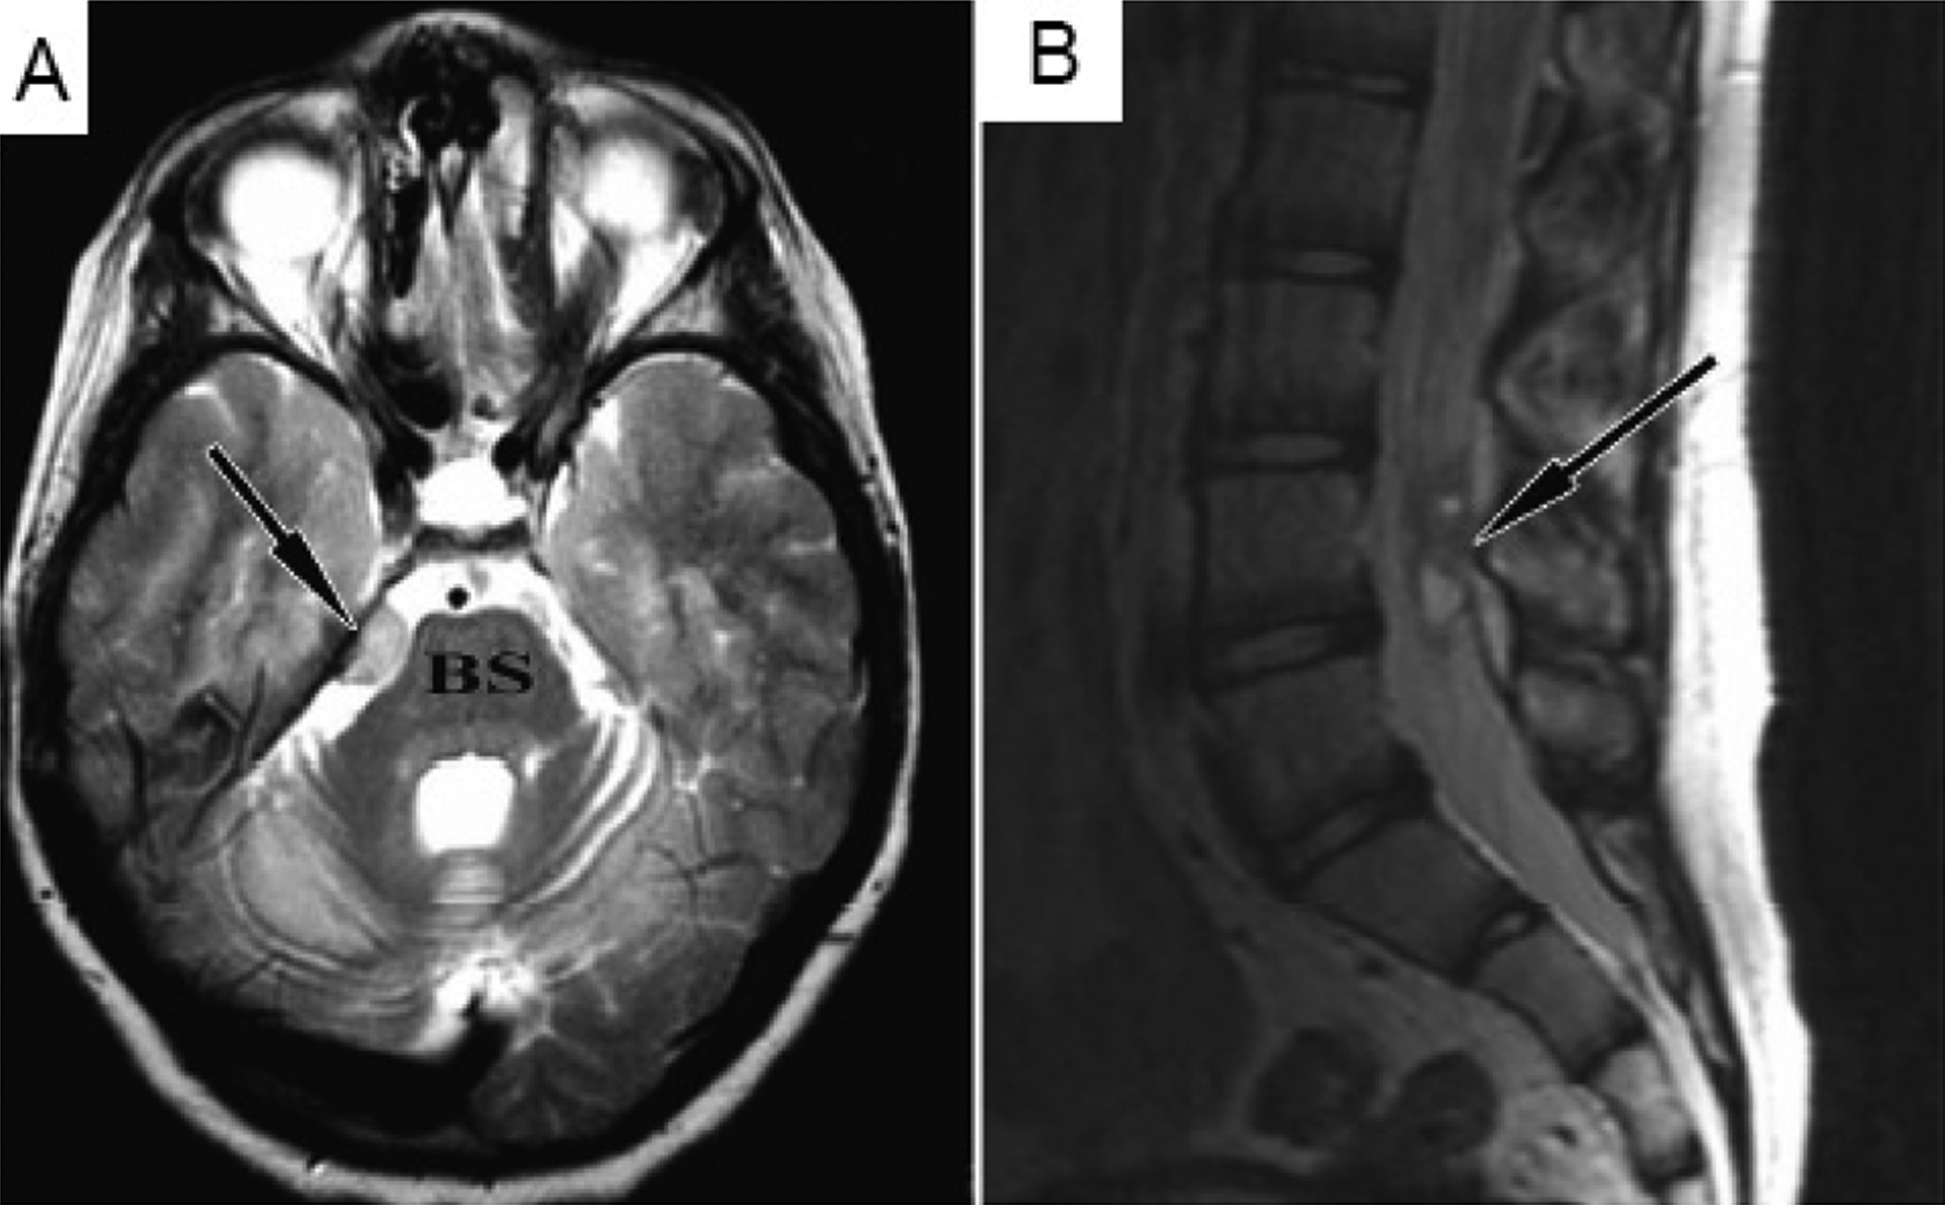

An unregulated stem cell treatment in 2001 led to tumor growth in the (A) brain stem and (B) spinal cord of the patient four years later. (Fig 1. PLoS Med. 2009 Feb 17;6(2):e1000029)

Back in 2001, an Israeli boy suffering from Ataxia Telangiectasia, a genetic brain disease that affects movement, traveled to Russia for an unregulated stem cell treatment. His brain and spinal cord were injected with fetal stem cells though the exact composition of those cells was not known. Four years later, the boy complained of headaches and his doctors back home found tumors in his brain and spinal cord.

As the BBC and many other news outlets reported in 2009, a Plos Medicine report eventually confirmed the tumor cells originated from the donor stem cells. And here lies a double-edged sword of stem cell-based therapies. On one side, stem cells hold great promise to repair diseased or damaged tissue because they can morph, or differentiate, into a wide range of cell types.